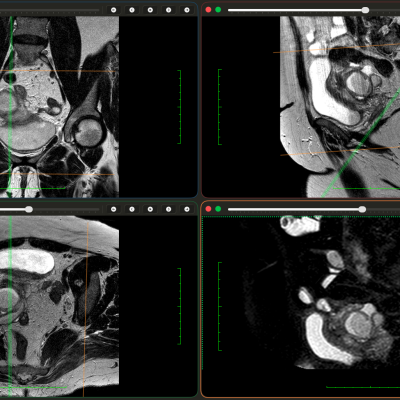

✔ розбір МРТ та клінічного висновку (зображення будуть доступні на сайті)